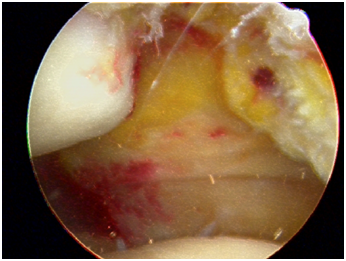

Diagnostic arthroscopy is used to define all intra-articular pathology. Soft tissue injuries including partial meniscal tears, synovitis and chondromalacia are addressed first, followed by osteochondral defects along the patella and/or lateral femoral condyle. Depending on the extent of the chondral injury and the quality and size of the detached fragment (Figure 1), either internal fixation of the fragment or a microdrilling technique is employed. If internal fixation was employed, often the pathology was addressed after the arthroscopic procedure was completed. The medial border of the patella is evaluated arthroscopically. Finally, a medial parapatellar incision measuring 3 to 4 cm is made. Dissection is carried through the skin, subcutaneous tissue and musculo-ligamentous structures until the MPFL remnant is identified. The ligament is assessed at both the patellar and femoral insertions. In the cases reviewed here, the remnant was large enough to be repaired using six to eight 2-0 poly (ethylene, terephthalate) sutures, using a pants-over-vest technique with the knee in 30° of flexion (Figure 2). The tears were found to be midsubstance and not avulsed from either the patella or femoral insertion. A varus stress is then applied to the patella to confirm adequate tensioning of the repair before the knee is taken through the full range of motion to assess patellar tracking. A standard closure of the subcutaneous tissues (Figure 3) is performed with 2-0 Vicryl (polyglactin 910; Ethicon, Somerville, NJ) before the skin is closed with a running Monocryl stitch (poliglecaprone 25; Ethicon). At the conclusion of the surgery, the knee is placed in an immobilizer, which the patient must wear until the first postoperative visit.

Figure 2 Medial patellofemoral ligament repair using suture.